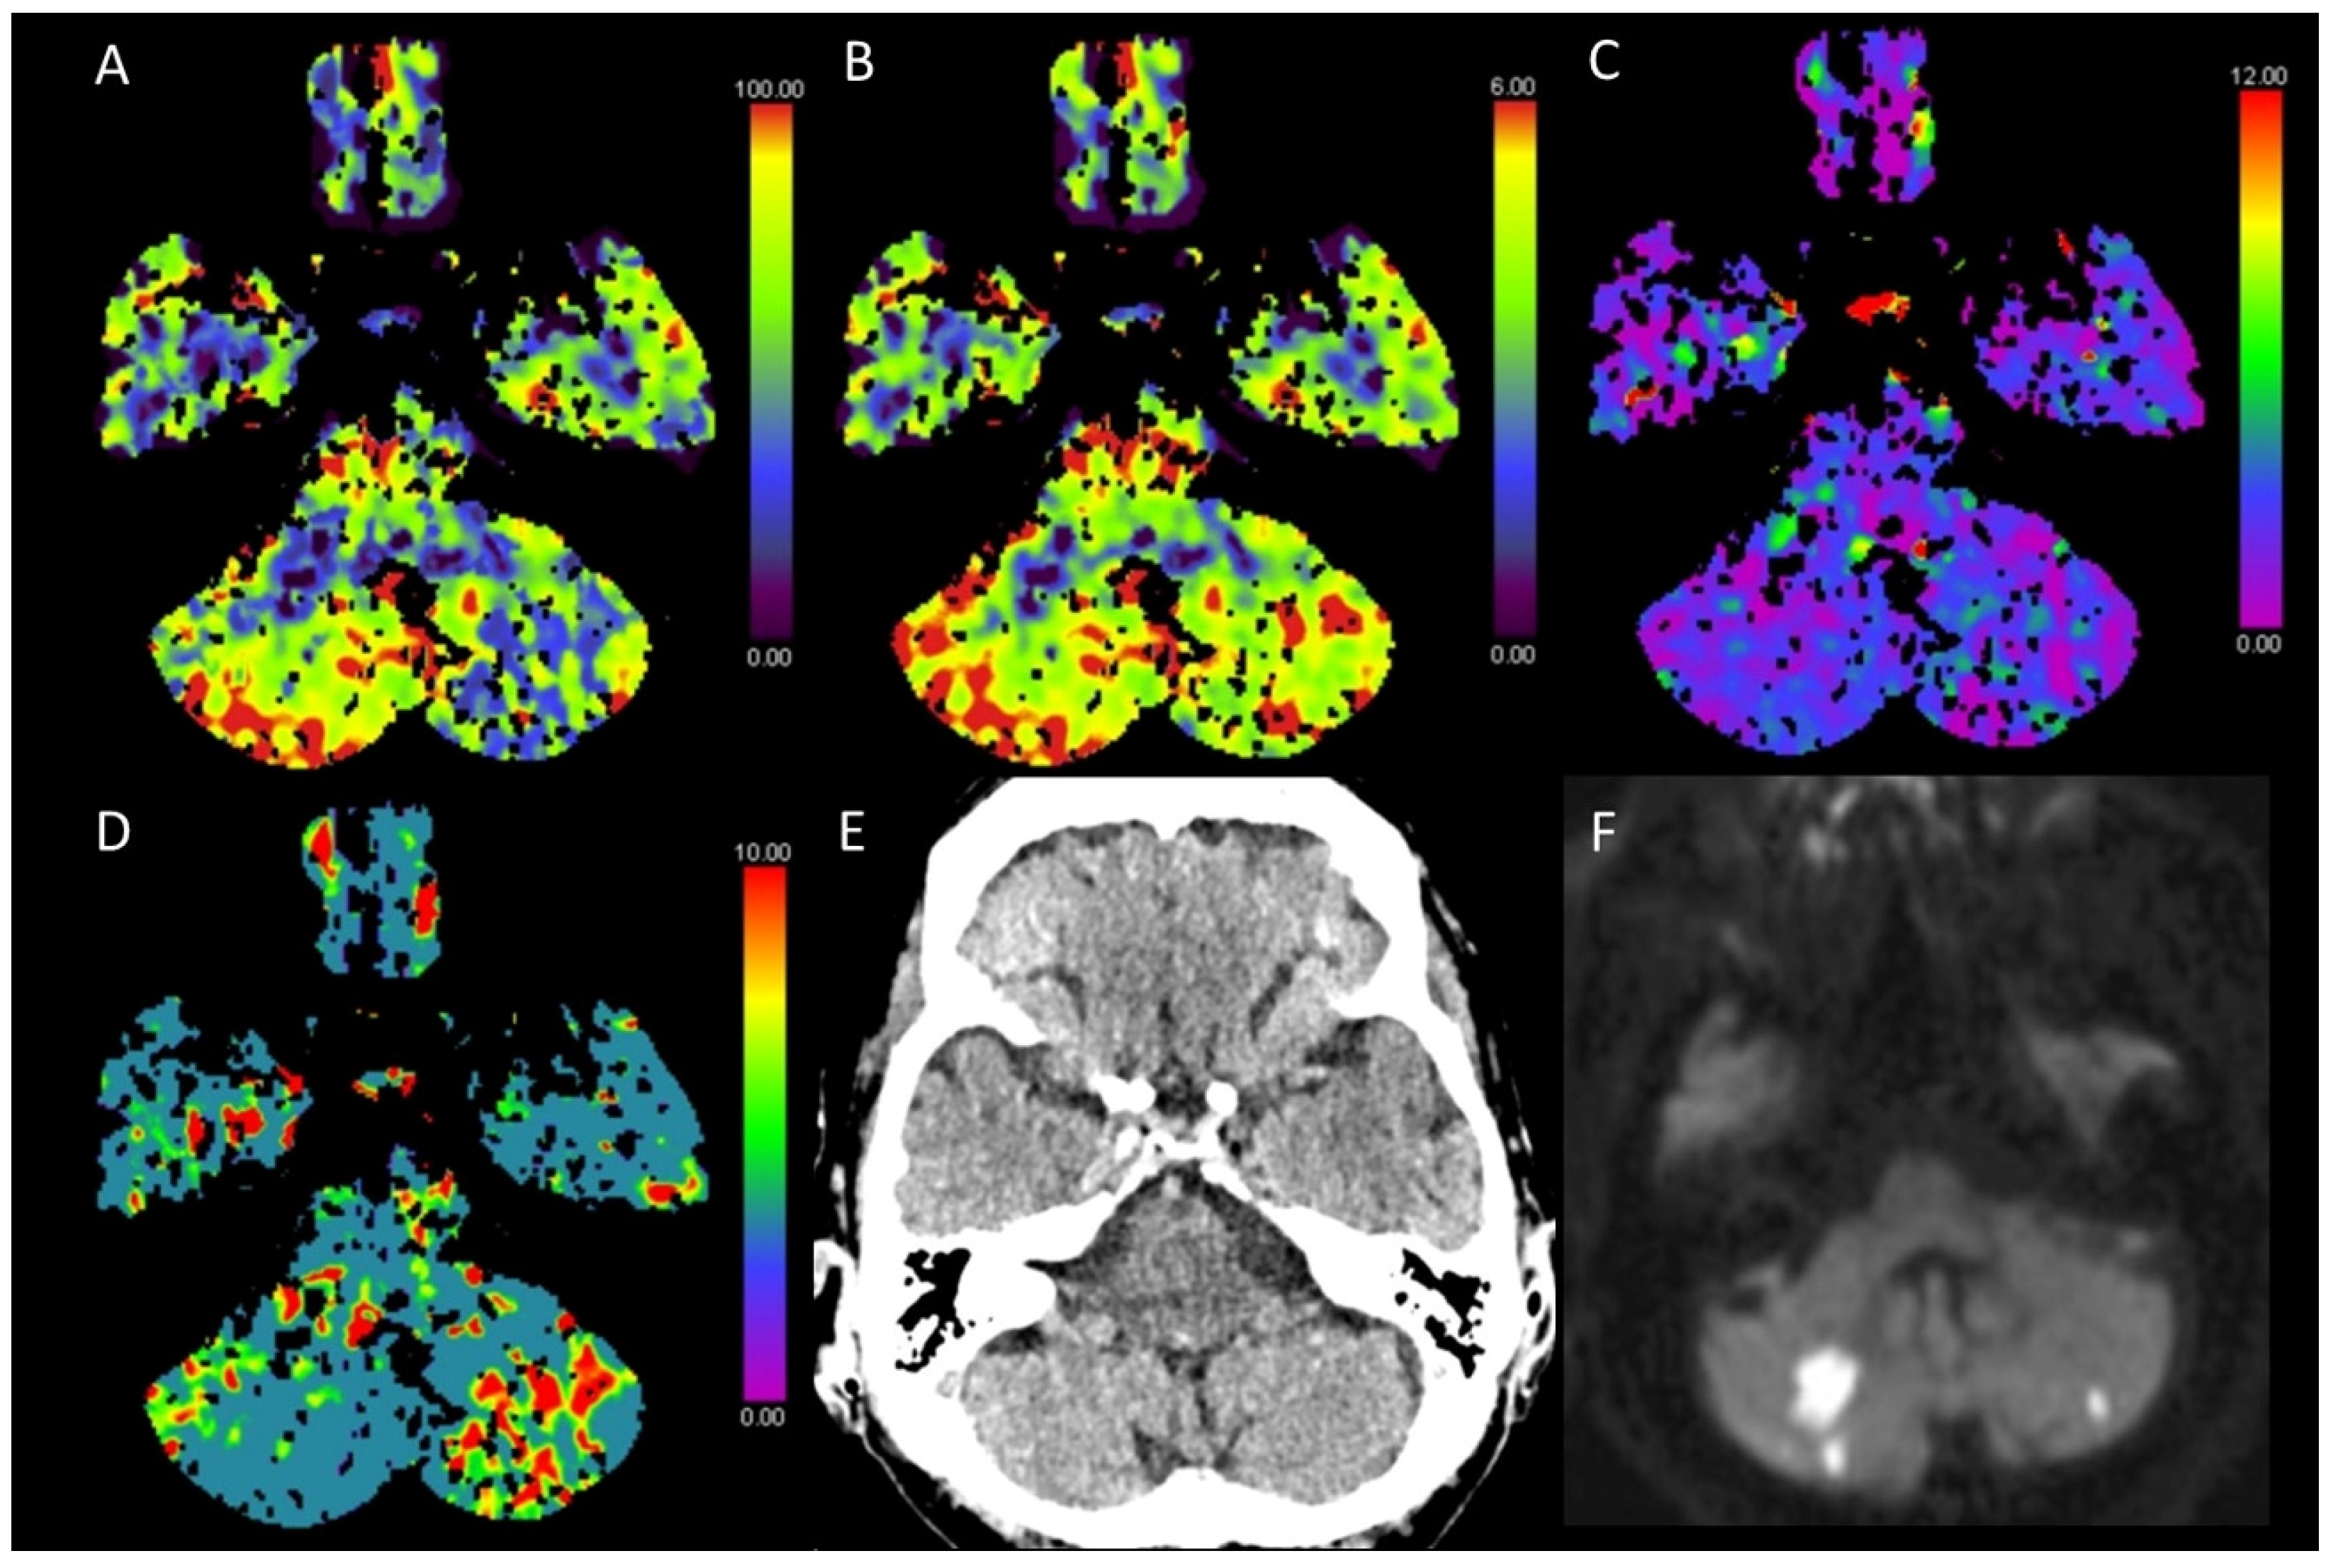

3.2. Acute Posterior Fossa Infarcts